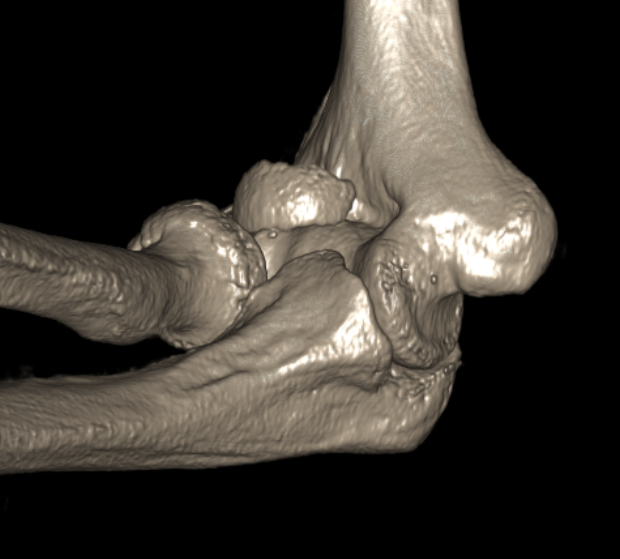

Dubberly Classification

| Type I | Type Ii | Type III |

|

Capitellar fracture

Capitellum + trochlea fracture In one piece Double arc sign seen on xray |

Capitellum + trochlea fractures In two separate pieces |

Concomitant injuries

Radial head

- 79 capitellar fractures

- 24% had a radial head fracture as well

LCL

- 27 capitellum fractures treated with surgery

- 41% had associated LCL injuries

- 7/11 LCL injuries were avulsion fractures of the lateral epicondyle